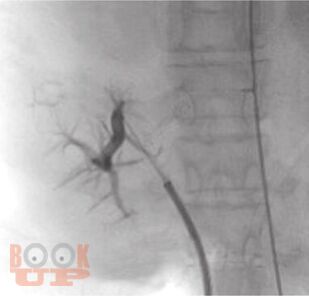

В монографии представлены алгоритмы периоперационного ведения пациентов с циррозом печени, стандарты диагностики, предоперационной подготовки и послеоперационной реабилитации. Рассмотрены принципы формирования и тактика ведения листа ожидания трансплантации печени, а также технология проведения хирургического вмешательства.

Проанализированы выявленные ошибки и предложен междисциплинарный подход в тактике периоперационного ведения пациентов с участием хирургов, гастроэнтерологов, эндоскопистов, эндоваскулярных хирургов.